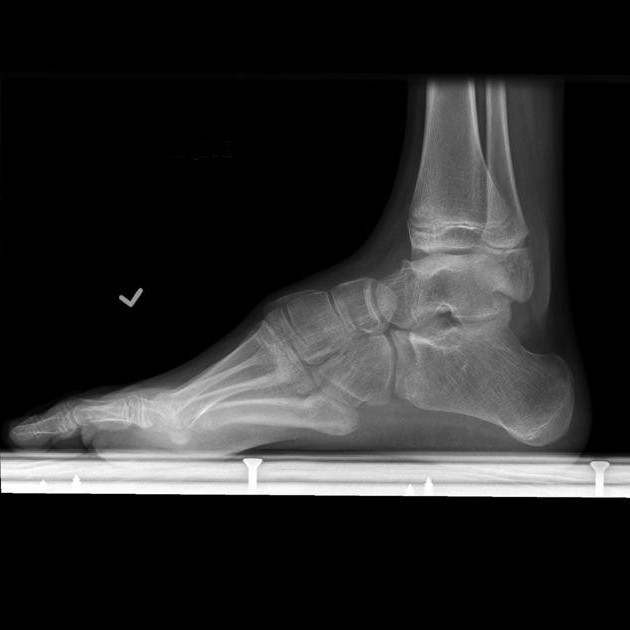

Le diagnostic des pieds plats inclut l’écoute des plaintes, l’examen de l’état externe du pied et sa détection. Le diagnostic est clarifié à l'aide d'une radiographie. Ayant une radiographie, le médecin détermine le type et le stade de la maladie. Ainsi, la question de savoir s'ils prennent 3 degrés à l'armée avec les pieds plats est possible de répondre négativement, en ayant en main des images des pieds et la conclusion de l'orthopédiste. Il existe également un moyen simple de déterminer si une recrue a une maladie. C'est une méthode plante-gamma. Pour ce faire, la plante du pied est peinte avec une peinture inoffensive, après quoi une empreinte est placée sur une feuille de papier. Après analyse de la trace, nous pouvons juger de la présence et du degré de la maladie et, en conséquence, déterminer s’ils prennent les pieds à plat dans l’armée.